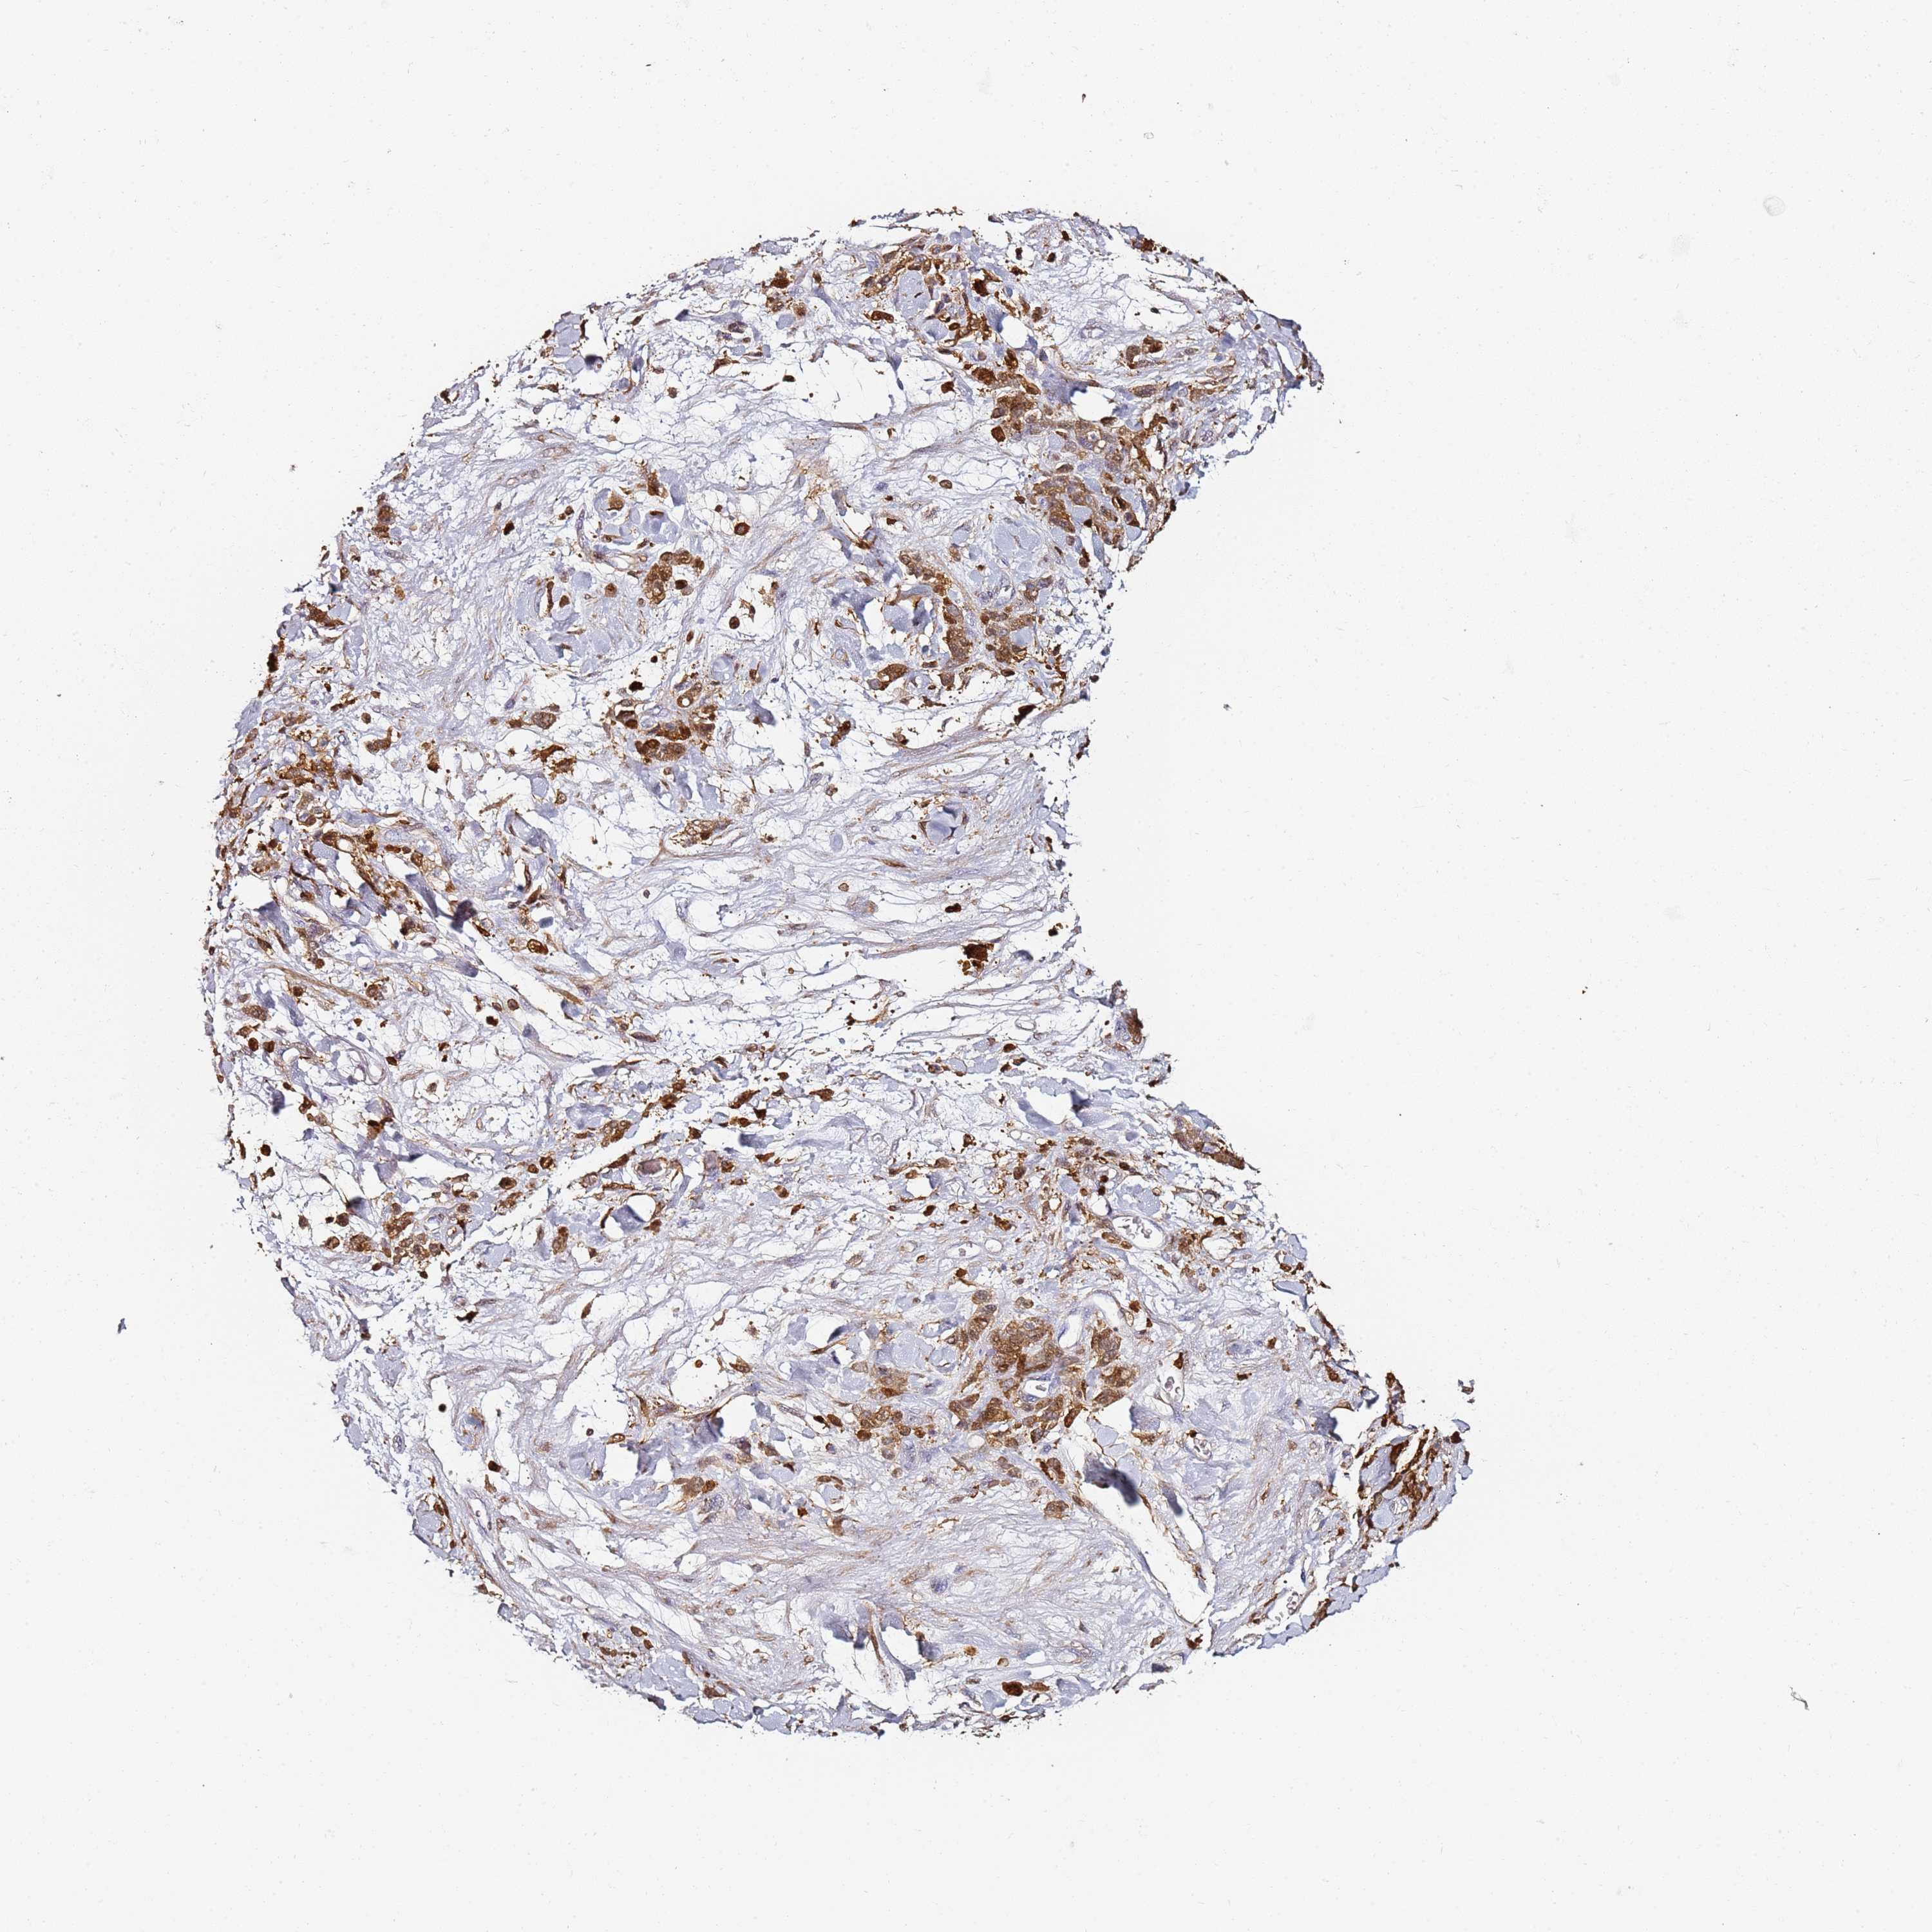

STOMACH CANCER - Protein expressioni

A mouse-over function shows sample information and annotation data. Click on an image to view it in a full screen mode. Samples can be filtered based on level of antibody staining by selecting one or several of the following categories: high, medium, low and not detected. The assay and annotation is described here.

Note that samples used for immunohistochemistry by the Human Protein Atlas do not correspond to samples in the TCGA dataset.

Antibody stainingi

Antibody staining in the annotated cell types in the current human tissue is reported as not detected, low, medium, or high, based on conventional immunohistochemistry profiling in selected tissues. This score is based on the combination of the staining intensity and fraction of stained cells.

Each image is clickable and will lead to virtual microscopy that enables deeper exploration of all samples and also displays staining intensity scores, fraction scores and subcellular localization as well as patient and tissue information for each sample.

HPA007973

CAB002618

CAB027387

CAB058698

CAB068227

CAB068228

Adenocarcinoma, NOS